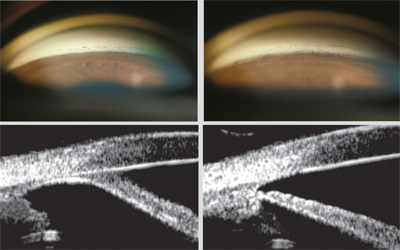

6. 백내장 수정체 적출술

백내장 수술 즉 수정체 적출술 및 인공수정체 삽입술 만으로도,

폐쇄각녹내장치료에 도움이됩니다.

폐쇄각 녹내장의 원인 자체가 수정체의 팽대로 인한 수정체-홍채의 접촉이기에,

팽대된 백내장을 제거하고 , 얇은 인공수정체로 교환하면, 폐쇄각 녹내장이 치료됩니다.